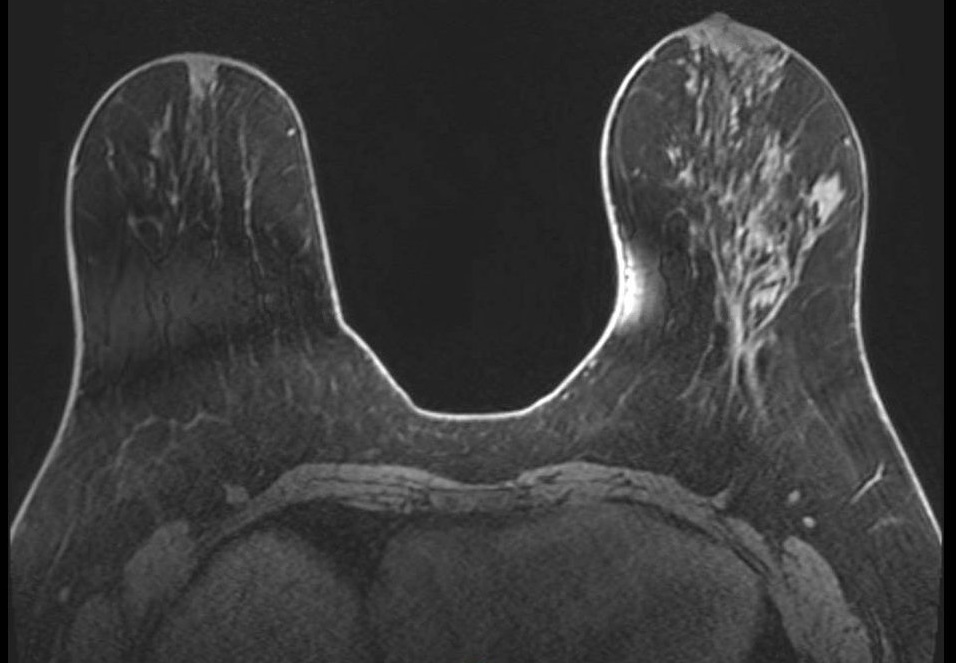

Gibbs Ring Artifact (Truncation Artifact)

Key Points

- Arises from Fourier truncation of finite k-space data

- Appears as parallel ringing bands at high-contrast interfaces (skin-air, skin-parenchyma, implant margins)

- More pronounced in the phase-encode direction

- Most visible on high-contrast sequences such as T2-weighted imaging

- Fix: increase phase-encode steps; zero-fill interpolation

In breast MRI, it is easiest to see at skin-air, skin-parenchyma, and implant margins, especially in the phase-encode direction and on high-contrast sequences (e.g., T2). Reduce it by increasing phase-encode steps (more k-space lines) at scan-time cost; zero-fill interpolation can smooth the appearance but does not recover true spatial resolution. Recognition of the characteristic parallel-band pattern of Gibbs ringing helps differentiate it from true lesions.

Gibbs ring artifact most noticable at implant interface (axial, IR sequence)

Gibbs ringing is a Fourier truncation artifact from finite k-space sampling. Inverse FFT of truncated data fails to represent the highest spatial frequencies at abrupt transitions, generating thin parallel bright/dark bands near high-contrast boundaries.